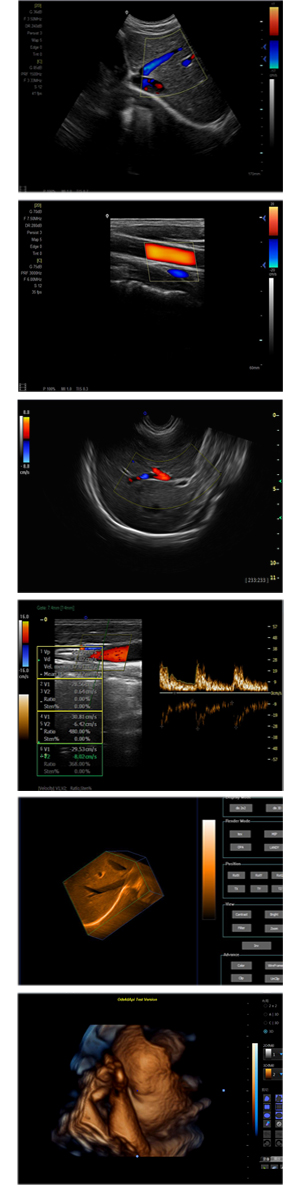

XF-7600型,秉承先鋒彩超技術(shù)之精華,擁有高雅大氣的獨特外型,為最新一代應(yīng)用型數(shù)字彩色多普勒診斷系統(tǒng),魅力與實力相融合??蓮V泛適用于腹部、婦產(chǎn)科、心臟、小器官、乳腺、肌骨及外周血管等諸多方面的診查,讓您在臨床超聲診斷應(yīng)用領(lǐng)域得心應(yīng)手,綻放異彩!

● 3D/ 4D成像技術(shù)/選配

● 應(yīng)用于腹部、腎臟、泌尿系統(tǒng)、產(chǎn)科、婦科、盆腔、大動脈、肌肉組織、小器官、乳腺、心臟等

● 能量多普勒成像(PDI)

● 彩色血流量圖(CDE)

● 脈沖頻譜多普勒成像(PW)